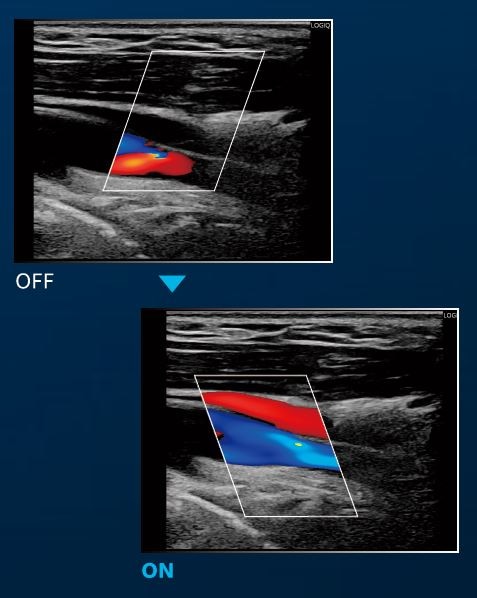

HDC (High Definition Color)

高いフレームレートにより組織のフラッシュアーチファクトを低減し、超低流速の血流であっても鮮明な表示を可能としました。

ROI内のBモード画像上に、 高精細フローイメージを重ねて表示できます。